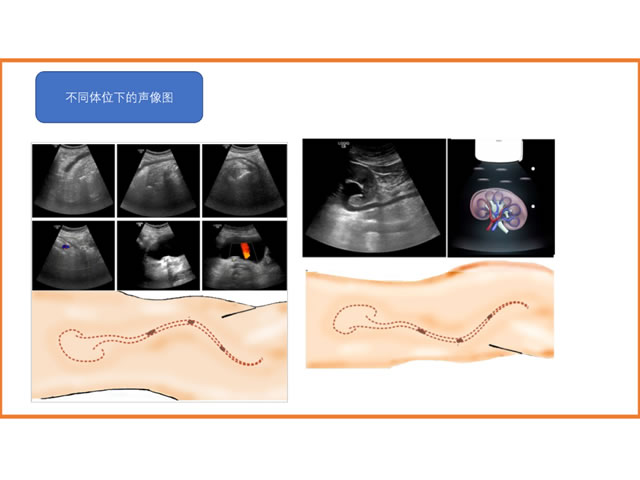

今天,我们回顾吕建林主任在多尼尔中国行——南京站暨ESWL超声定位科室交流会上的精彩演讲。他的演讲题目为:输尿管中下段结石超声定位ESWL。以下是他的讲课课件。

输尿管中下段结石超声定位ESWL